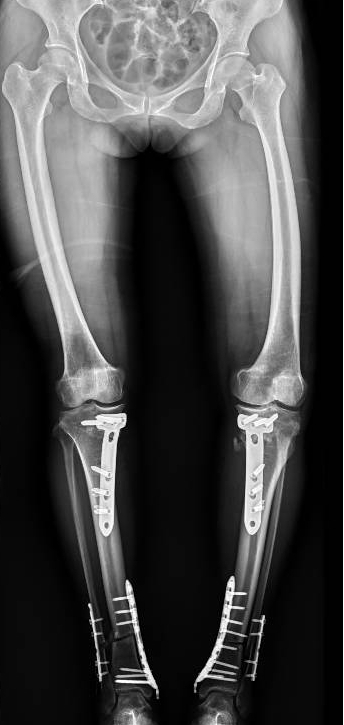

李彬在詳細(xì)了解了董阿姨的病史、進(jìn)行了全面的體格檢查和相關(guān)的輔助檢查后,組織科室進(jìn)行了深入的討論。最終的“答案”是——雙膝骨性關(guān)節(jié)炎、雙膝關(guān)節(jié)畸形、骨質(zhì)疏松以及雙膝半月板損傷。

面對(duì)這樣復(fù)雜且嚴(yán)重的病情,李彬并沒(méi)有退縮。他深知,對(duì)于董阿姨來(lái)說(shuō),這不僅僅是一次手術(shù),更是一次重生的機(jī)會(huì)。因此,他精心制定了手術(shù)方案:對(duì)雙下肢脛骨近端、遠(yuǎn)端以及雙側(cè)腓骨遠(yuǎn)端進(jìn)行截骨矯形,并進(jìn)行植骨內(nèi)固定。這樣的手術(shù)方案,無(wú)疑是對(duì)醫(yī)生技術(shù)的一次高難度挑戰(zhàn)!

手術(shù)前 手術(shù)后

手術(shù)很成功!經(jīng)過(guò)精心的治療和護(hù)理,董阿姨在9月順利出院。當(dāng)她再次站在鏡前時(shí),她驚喜地發(fā)現(xiàn)自己仿佛長(zhǎng)高了一截,那份曾經(jīng)讓她備受折磨的疼痛與不適也逐漸消失了。